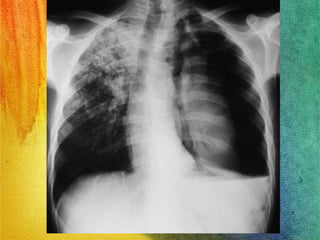

TBC: Diagnóstico: Rx Tórax

• Manifestaciones variadas e inespecíficas.

TBC Primaria:

 Linfoadenopatías.

 Opacidades

parenquimatosas, tanto

del espacio aéreo como

del intersticio, siendo la

consolidación del espacio

aéreo el patrón radiológico

más común, acompañado

en ocasiones de

excavaciones

Guías clínicas de tuberculosis OMS 2010

Compromete con

mayor frecuencia

segmento apical o

posterior de lóbulos

superiores.

RADIOLOGIA

Complejo de Ghon es la presencia de una

pequeña zona radiopaca por debajo de la

clavícula derecha, junto a una calcificación

a nivel de los ganglios linfáticos hilares,

unidos por un trazo lineal.

Algunas lesiones curan mediante fibrosis y

calcificación

• Nódulos de Simón;

formaciones nodulares

apicales bilaterales y

simétricas

• Infiltrados:

• De tipo nuboso o moteado,

muchas veces ubicadas en el

íleo, lesión intensamente

inflamatoria

• Imagen en tienda de

campaña radiopaca en las

bases pulmonares, puede

tener fibrosis

• Cavitación: zona radiolucida

en el centro , localizada

sobre todo en los vértices

pulmonares